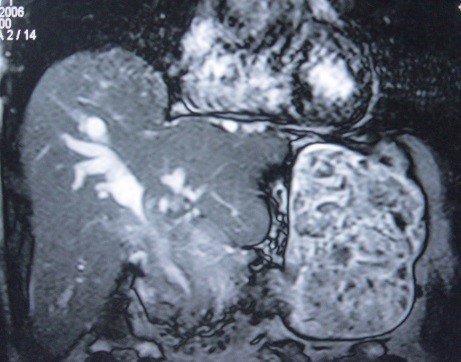

- Zədələnmələrin olub-olmamasını, yеrini və xaraktеrini dəqiqləşdirmək üçün xolangioqrafiya еdilir. MRT ilk seçimdir, lakin dəqiqləşdirmə üçün adətən kontrastlı xolangioqrafiya edilir: əməliyyat vaxtı əməliyyatdaxili xolangioqrafiya, əməliyyatdan sonra isə endoskopik və ya perkutan xolangioqrafiya.

- Öd yollarına yeridilən kontrastın kənara çıxması və ya “blok” (bağlanma) zədələnməni təsdiqləyən əlamətləridir.

Diaqnostik əlamətlər:

- Biliar sızıntı (peritonit, fistul, bilioma, qaraciyərdaxili abseslər) və / və ya mexaniki sarılıq

- Xolangioqrafiyada biliar ekstravazasiya və ya blok

Əməliyyatdan sonra tapılan bağlamalarda xəstə ixtisaslaşmış klinikaya göndərilir. Belə xəstələrdə ilk olaraq MRT edilərək bağlanma yeri dəqiqləşdirilir. MRT yetərsiz olarsa ERXPQ edilə bilər. Əlavə olaraq KT angioqrafiya və ya dopler USM ilə arteriya zədələnməsini yoxlamaq lazımdır. Diaqnostik işləmlərdən sonra zədələnmə yerinə və ağırlaşmalara görə müalicə taktikası seçilir. Magistral axacaqların bağlanmasında xəstə nəzarət altında saxlanılır, anastomoz üçün 2-3 həftə gözlənilir və ağırlaşmaların profilaktikası həyata keçirilir. Bu müddət öd yollarının genişlənməsi, divarının qalınlaşması, iltihabın sönməsi və anastomoz üçün əlverişli şərait yaratmaq məqsədi daşıyır. Gözləmə müddətində ağırlaşmaların profilaktikası və müalicəsi üçün aşağıdakı tədbirlər həyata keçirilir: